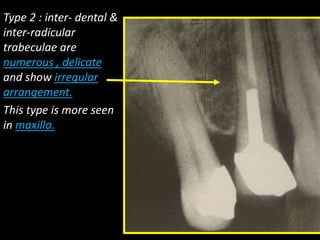

Type 2 : inter- dental &

inter-radicular

trabeculae are

numerous , delicate

and show irregular

arrangement.

This type is more seen

in maxilla.